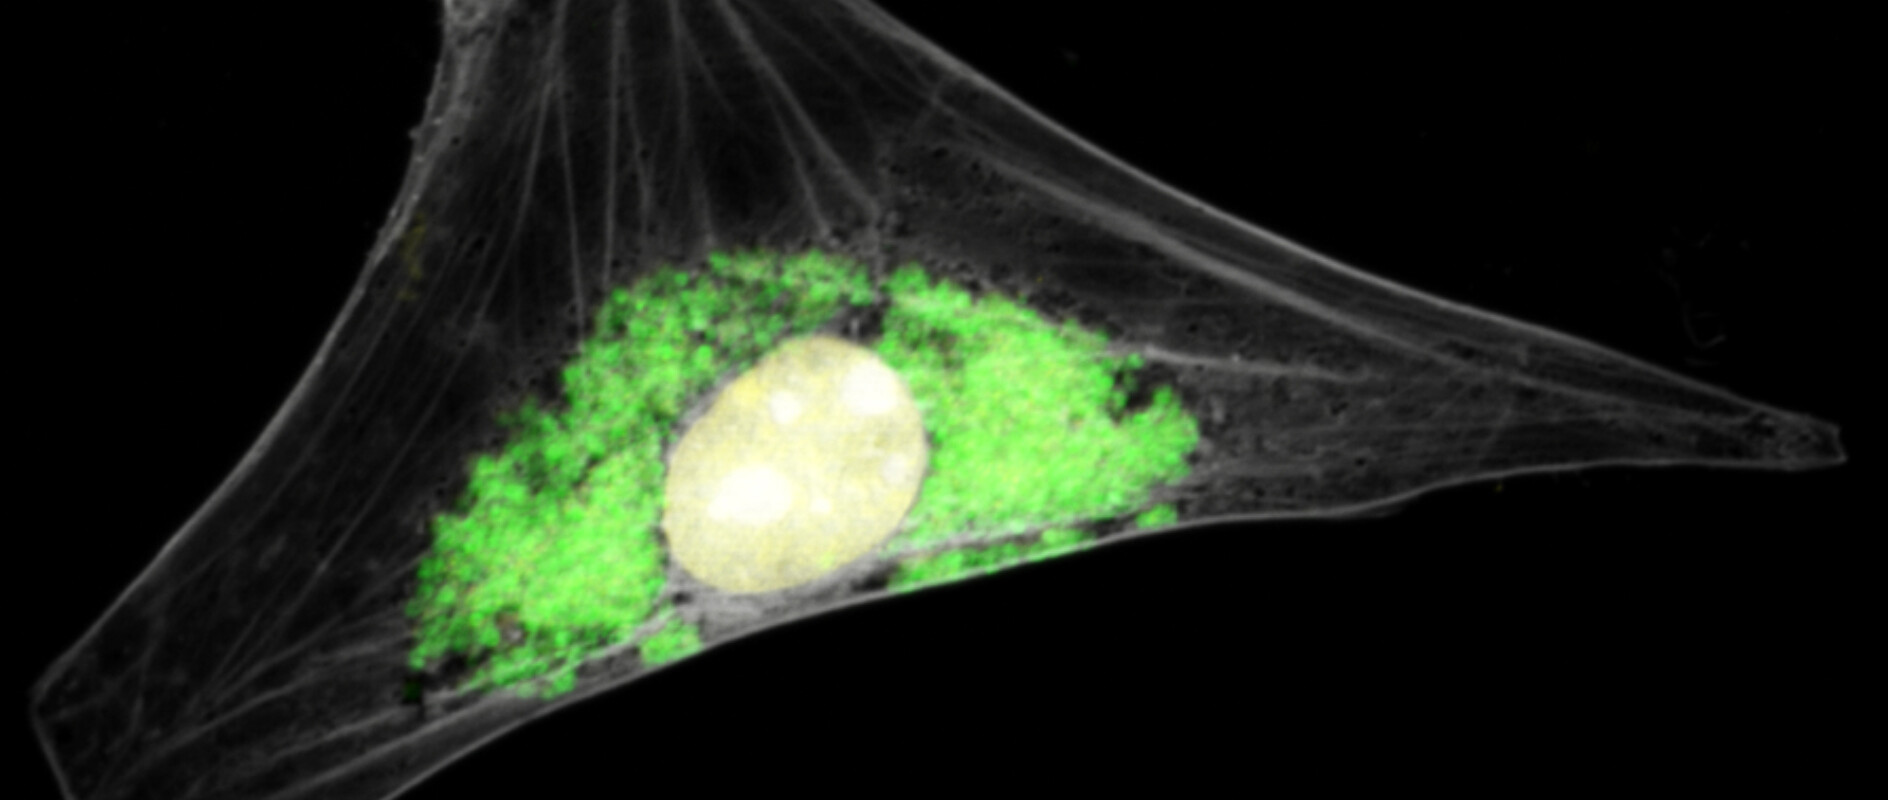

Image: Barbara Sixt, Eva-Maria Diehl, Copyright Barbara Sixt, The Laboratory for Molecular Infection Medicine Sweden, MIMS. The picture may only be used for information about the publication of Barbara Sixt in PLOS ONE: https://journals.plos.org/plosone/article?id=10.1371/journal.pone.0224324 corresponding author: barbara.sixt@umu.se